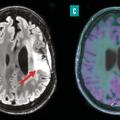

Perspectives en imagerie médicale oncologique

Le dépistage, le diagnostic et la prise en charge des cancers les plus fréquents, tels que le cancer du sein, de la prostate, du poumon et colo–rectal, reposent sur des avancées majeures en imagerie médicale. Grâce à des techniques performantes comme la mammographie, l’imagerie par résonance magnétique (IRM) multiparamétrique, la…